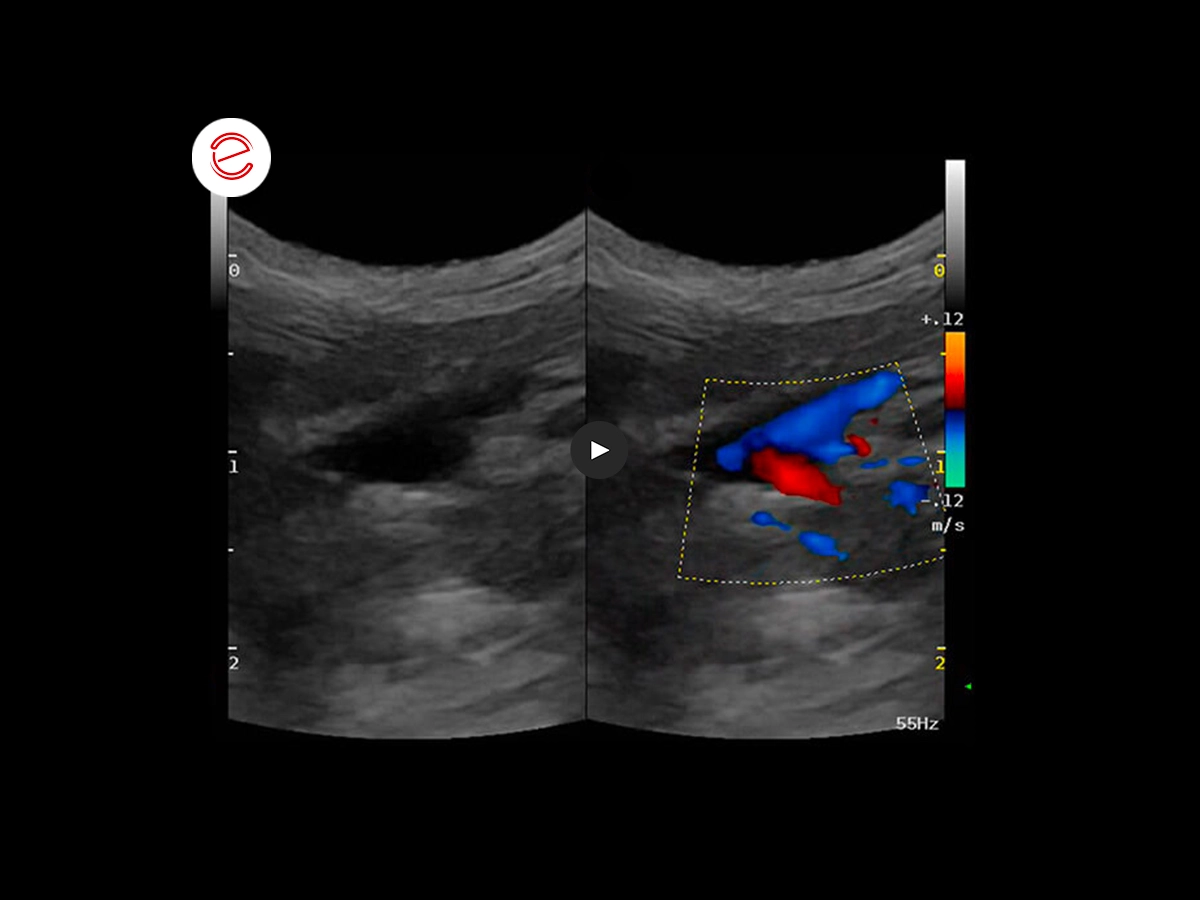

Con l'ecografia epatica sono stati valutati anche i flussi della vena porta e il flusso splenico è risultato invertito (codice colore blu).

Si sospettava uno shunt porto-sistemico e per confermarlo è stato eseguito un test di gorgogliamento inoculando nella milza una miscela agitata di sangue e soluzione fisiologica. Contemporaneamente è stata eseguita una valutazione cardiaca iniziale.

La valutazione, in concomitanza con il test di gorgogliamento, ha evidenziato piccole bolle iperecogene nell'atrio destro.